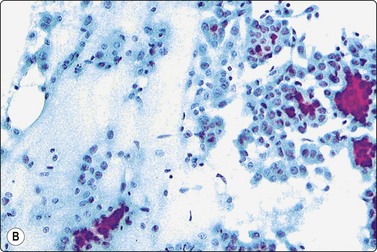

Fig. 7.3 Non-neoplastic glandular breast tissue and low-grade duct carcinoma

High-power view, air-dried smears; (A) Non-neoplastic glandular breast tissue; (B) Low-grade duct carcinoma. Note single bipolar nuclei in A, and absence of bipolar nuclei, relatively mild nuclear atypia and some loss of cohesion of malignant cells in B (MGG, HP).